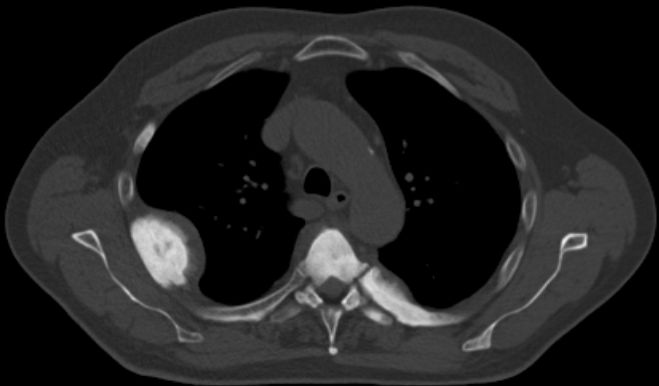

58-jähriger Mann mit Knochenmetastasen LWK3/4. PSA 911. Vor

einem Jahr Spondylodese LWK3-4. Bestrahlung. Jetzt Metastase BWK 6. Die

CT-Rekonstruktion zeigt zusätzlich mehrere Rippenmetastasen.![]() |

![]() | |||||||||||||||||||